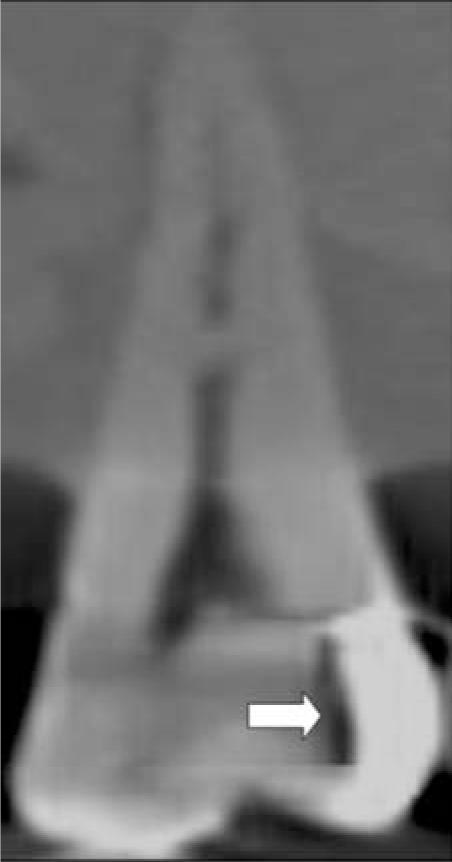

One hundred and twenty proximal slots of Class II cavities were randomly prepared on human premolar and molar teeth, and restored with amalgam (n=60) and composite resin (n=60). Then, artificial secondary caries lesions were randomly created using round steel No. 4 bur. The teeth were radiographed with a conventional bitewing technique and two CBCT systems; Pax-500ECT and Promax 3D. All images were evaluated by five observers. The area under the receiver operating characteristic (ROC) curve (A(z)) was used to evaluate the diagnostic accuracy. Significant difference was tested using the Friedman test (p value<0.05).

The mean A(z) values for bitewing, Pax-500ECT, and Promax 3D imaging systems were 0.882, 0.995, and 0.978, respectively. Significant differences were found between the two CBCT systems and film (p=0.007). For CBCT systems, the axial plane showed the greatest A(z) value.

Based on the design of this study, CBCT images were better than bitewing radiographs in detection of secondary caries.